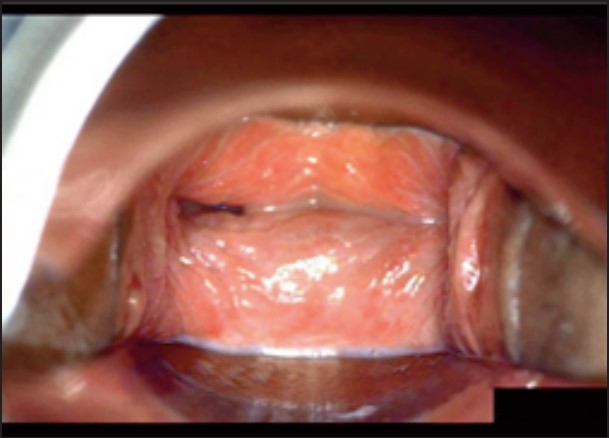

Під час спостереження до та після процедури, через 16 і 36 діб було зроблено вагінальні фотографії за допомогою Tele-Cervico (цервікографія) та виконано порівняння результатів до /після.

У пацієнток 1, 2 і 3 вагінальні складки утворилися та увиразнилися помітніше та сильніше, ніж вони були до лікування, ми оцінили цей клінічний результат після 1-го сеансу (через 16 діб). На нашу думку, такі виразні складки свідчать про підтяжку слизової оболонки піхви, що добре впливає на ущільнення піхви та проблему нетримання сечі. Через 36 діб після процедури ми спостерігали, що зруйнована анатомічна структура піхви відновила Н-подібну форму, тобто стала набагато здоровішою. Зокрема, у пацієнтки 4 структура піхви була цілковито зруйнована, стінки піхви обвисали через втрату еластичності. Однак через 36 днів після процедури структура піхви повністю відновила здорову Н-подібну форму [Див. Малюнок 3].

Пацієнтка №1

До

Після 36 діб